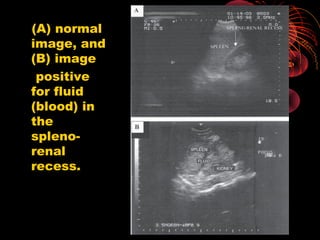

(Morison’s

pouch)

showing (A)

normal

(B)

hemoperitone

um, with fluid

(blood) in

Morison’s

pouch (arrow)

and anterior

to the liver.

(Morison’s pouch) showing (A) normal (B) hemoperitone um, withfluid (blood) in Morison’s pouch (arrow) and anterior to the liver.